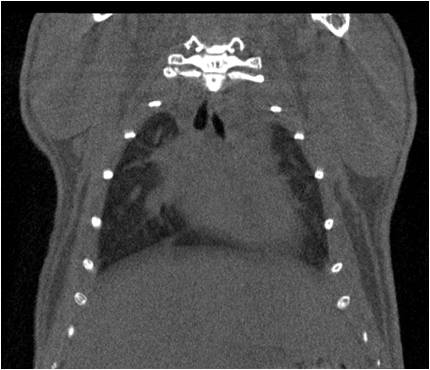

小鼠股骨

超高分辨率模式下像素大小為9μm。

A軸向和矢狀面顯示小鼠股骨結構。

B用鈦材料植入的穿過(guò)骨頭的冠狀切片